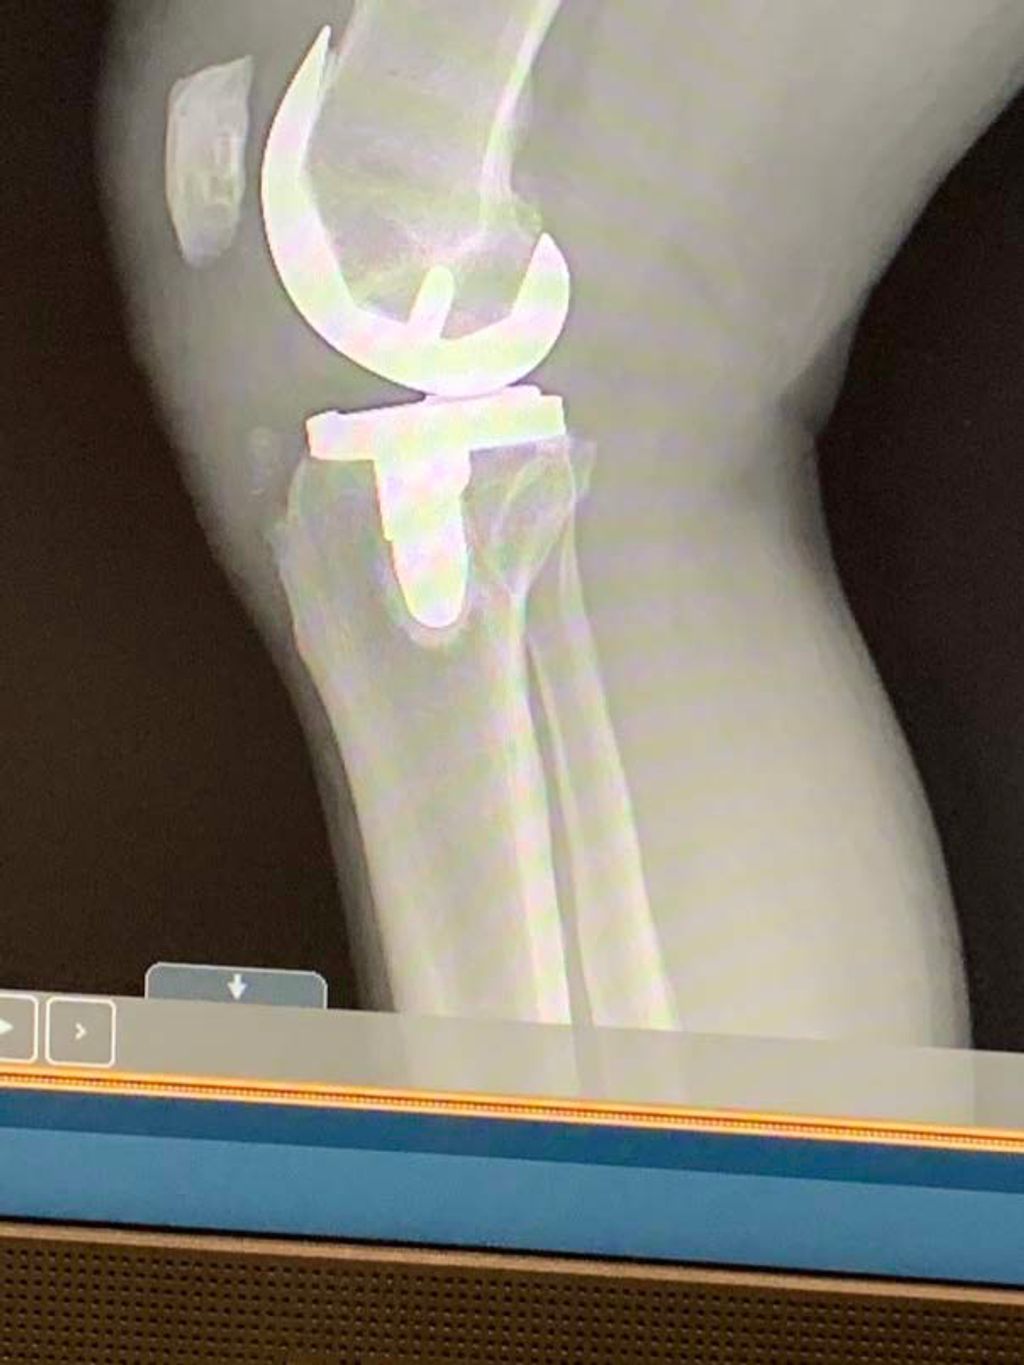

Surgical Interventions

When conservative management fails to provide relief or when the injury is severe, we often recommend surgical interventions. These procedures aim to repair or remove damaged tissue, thereby restoring function and alleviating pain. The most common surgeries for meniscus injuries are meniscectomy, where part of the meniscus is removed, and meniscus repair, which involves suturing the torn edges.

-

Meniscectomy is typically performed arthroscopically, a minimally invasive technique that reduces recovery time and postoperative complications. However, it’s important to note that removing meniscal tissue can increase the risk of osteoarthritis in the knee.

Meniscus repair is preferred when the tear is in the meniscus’s outer region, where blood supply is sufficient for healing. This procedure aims to preserve as much of the meniscus as possible, which is crucial for maintaining knee health and function.

Tip: Always discuss the potential risks and benefits of surgical options with your healthcare provider to make an informed decision about your treatment plan.